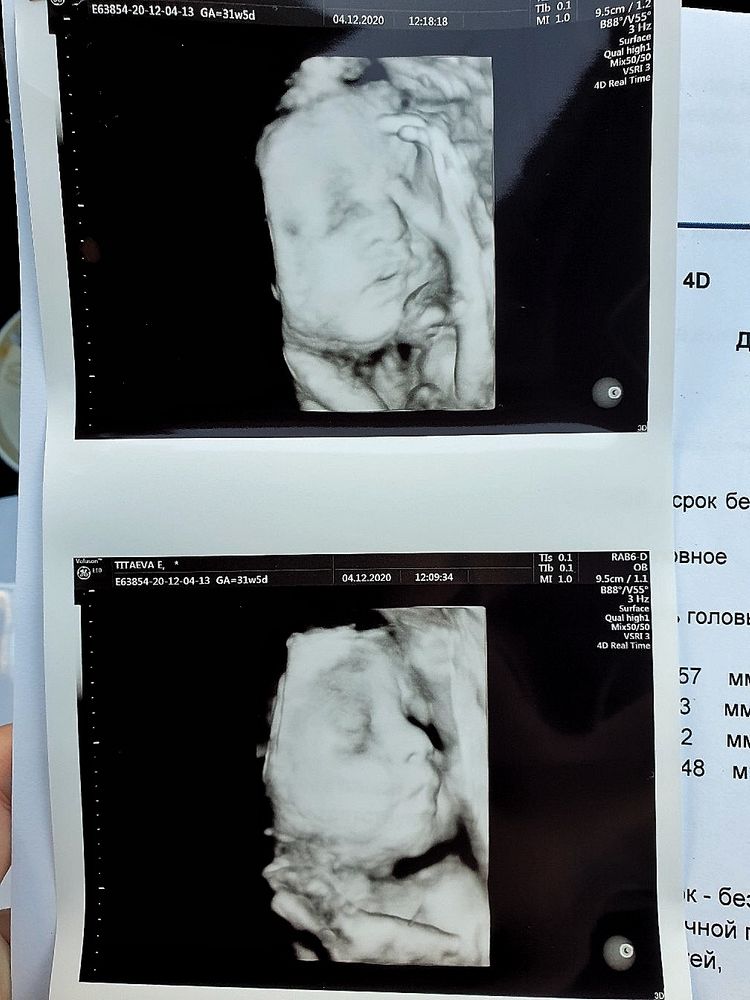

Делала в 31+5

Сегодня были на 3д. 33 неделя. Ничего толком не увидели. Ребенок ручками закрывал пол лица. Думаю, лучше конечно на 3д пораньше попасть. На поздних неделях очень тесно в животике, вот они и лежат там скрюченные.

спасибо за этот пост, я даже не думала, или уже забыла всё, что "поздно" может быть для 3Д)))) с первым ходила в 31 неделю, значит и в этот раз также пойдём)